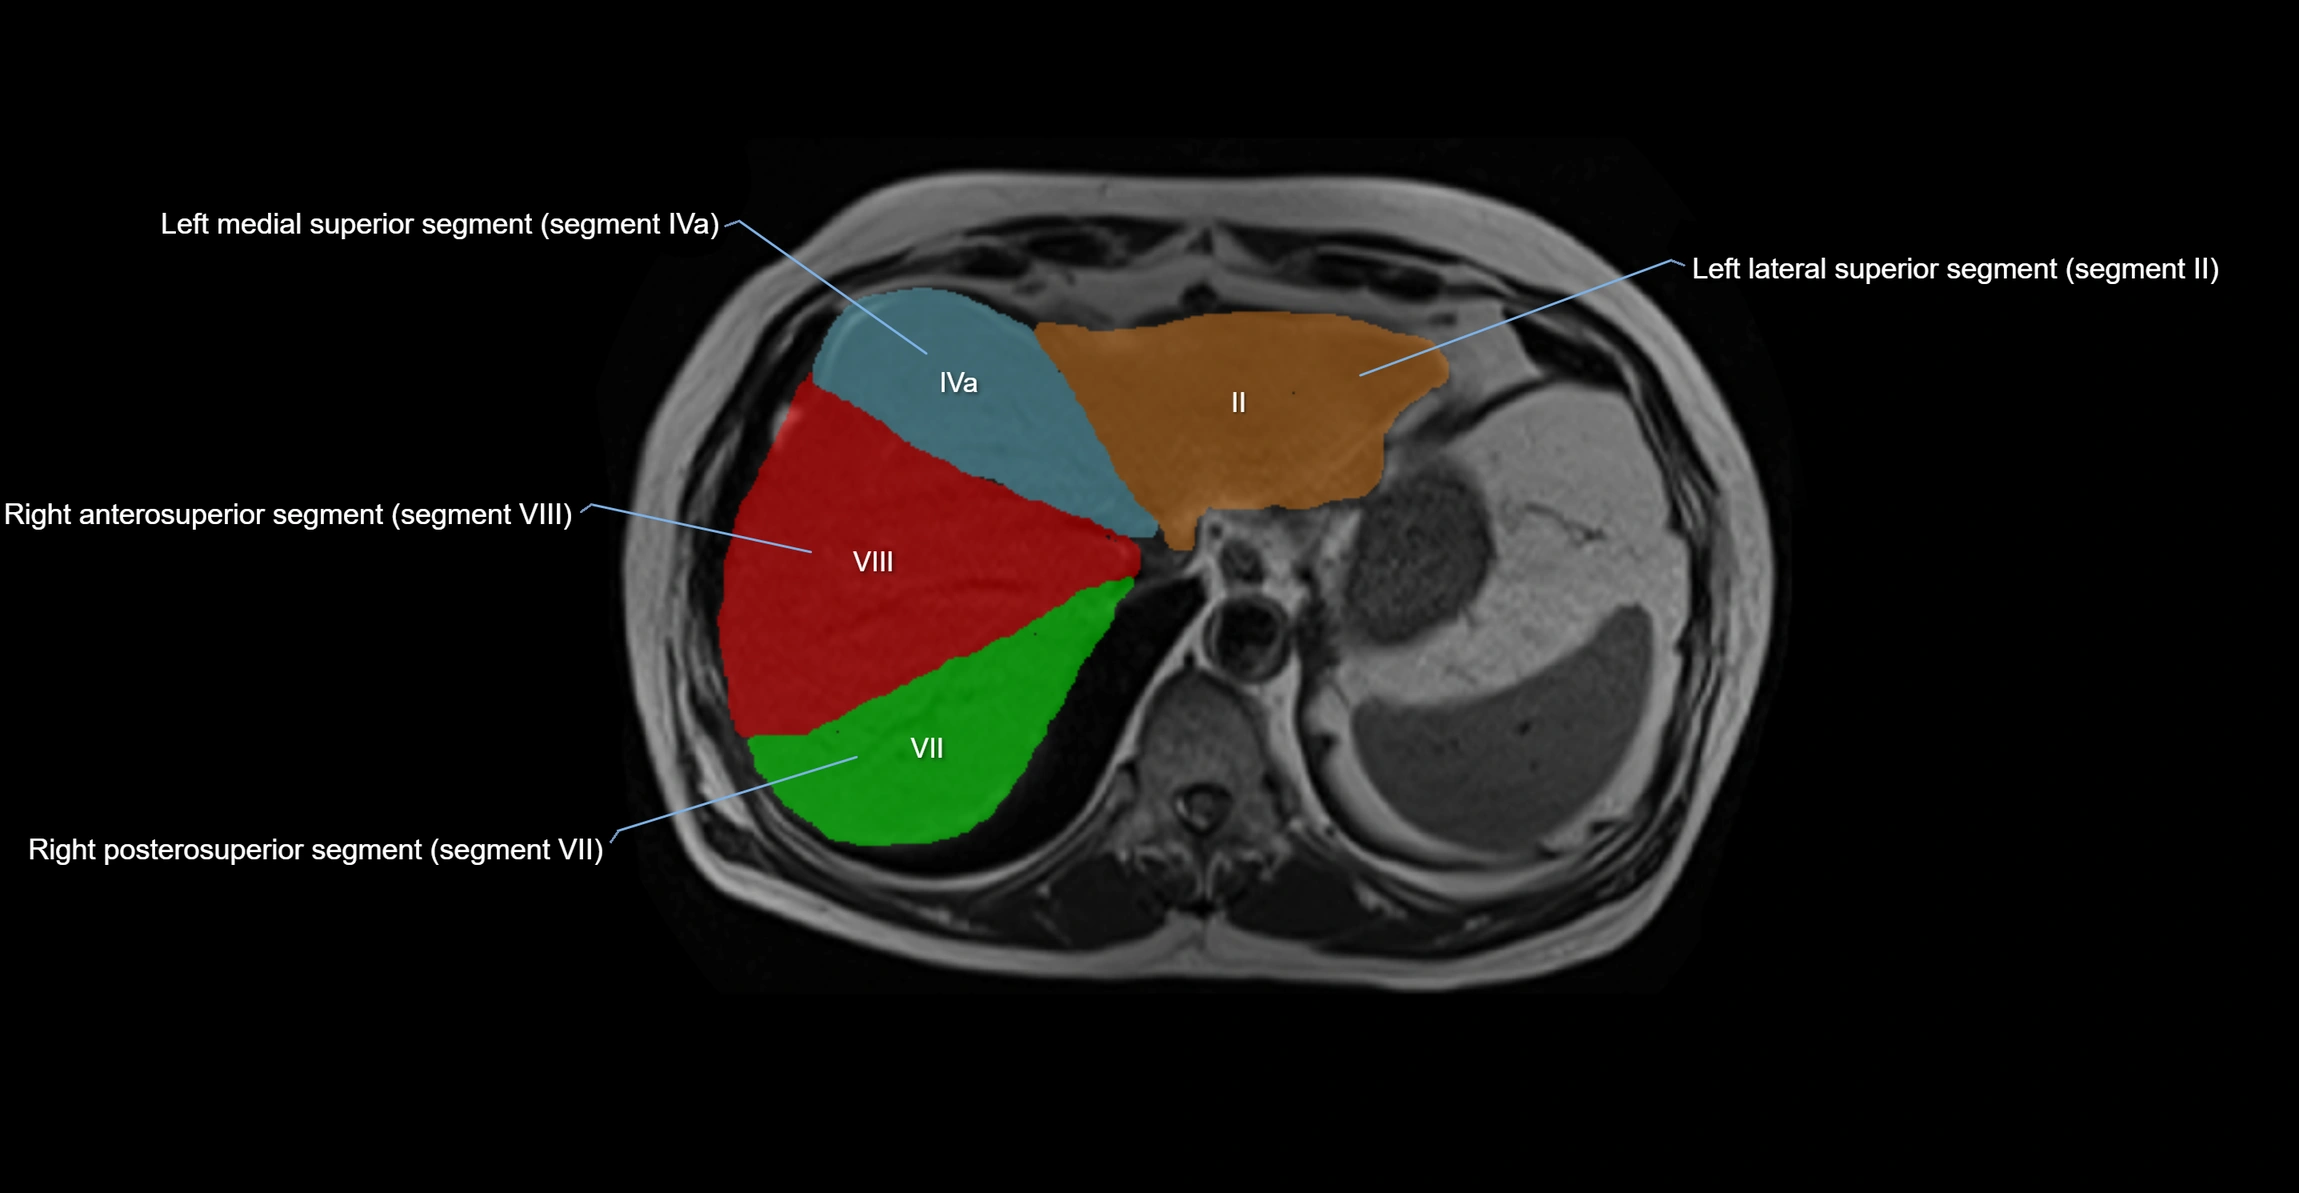

MRI image

image